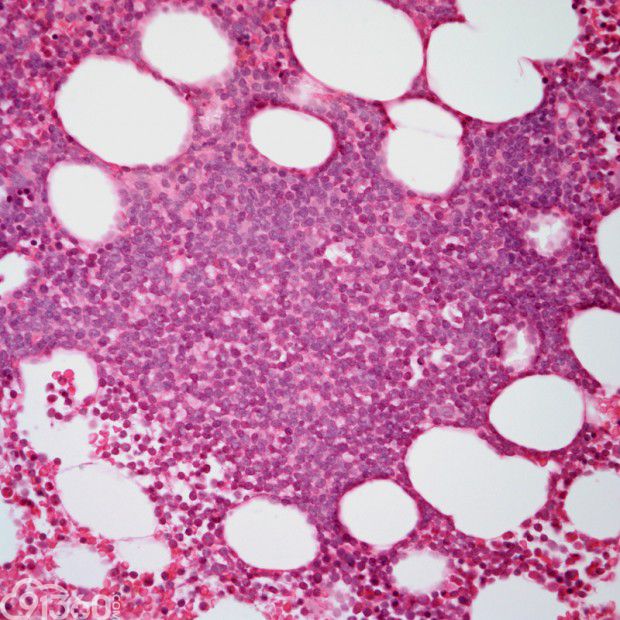

间变性大细胞淋巴瘤,ALK阳性 – 91360智慧病理网

ALK阳性间变性大细胞淋巴瘤 – 慧海拾穗博客 – 华夏病理网博客

教您识别慢性淋巴细胞白血病 – 91360智慧病理网

T淋巴细胞 – 91360智慧病理网